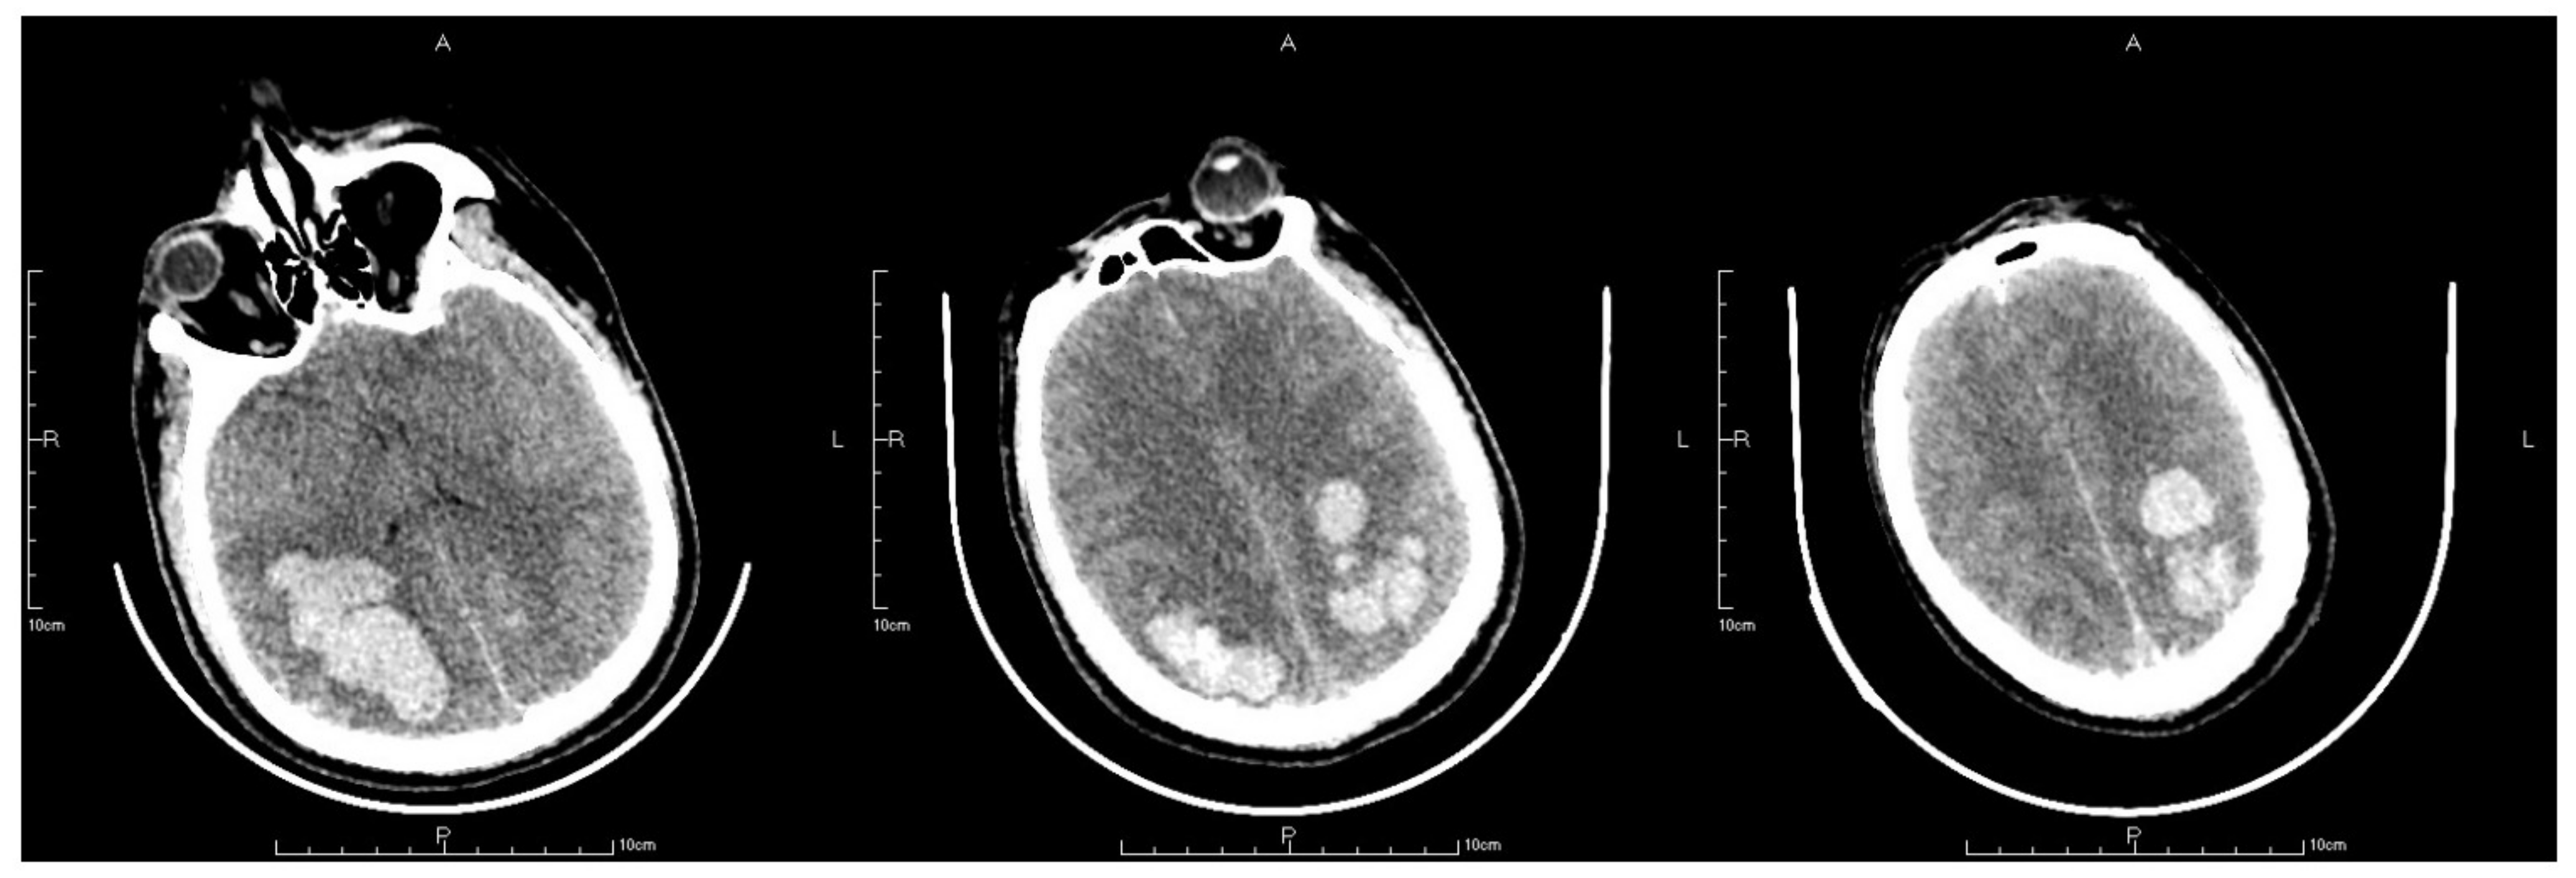

2. Case Presentation

2.4. Postoperative Management